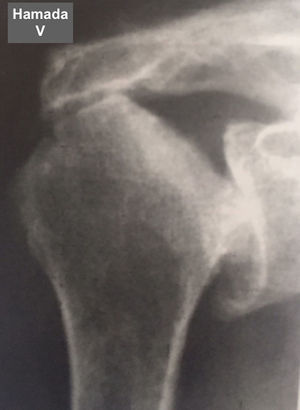

Fue elaborada por Hamada (tabla 6 y figs. 7–11) para describir el tipo de artropatía en roturas masivas del manguito de los rotadores. Utiliza la radiografía convencional y las características de la articulación glenohumeral y el ascenso de la cabeza del húmero para determinar el grado de la lesión. Muestra una correlación quirúrgica y radiológica de cerca del 80%10.